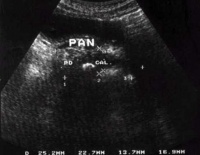

(3)腹部B超:可帮助诊断。B超扫描能发现胰腺水肿和胰周液体的积聚。还可探查胆囊结石胆管结石。但受局部充气肠袢的遮盖.限制了其应用。